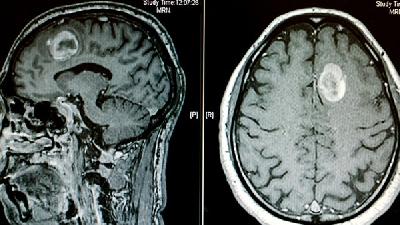

如果出现上述症状,应及时带孩子到医院做检查。如果诊断出脑瘫,需要测定智商,做脑电图的检查,以及CT、核磁等相关的影像学检查,从而判断脑部是否存在脑实或脑干的问题,然后再做进一步的治疗。